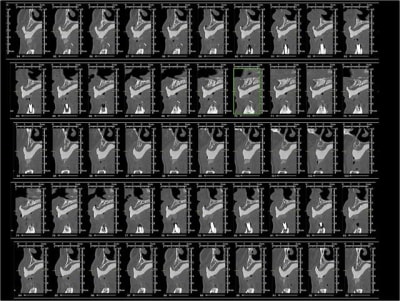

Tu veux dire une crête comme ça?

--

xbk

"Si tous ceux qui croient avoir raison n'avaient pas tort, la vérité ne serait pas loin" Dac Pierre